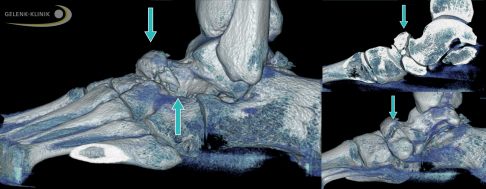

Die Schnittbilder der digitalen Volumentomografie (DVT) zeigen ein gebrochenes Kahnbein bei Müller-Weiss-Syndrom. Die Fraktur des Kahnbeins ist in der Seitenansicht des Fußes (links) und der Ansicht von oben (rechts) durch Pfeile gekennzeichnet. © Gelenk-Klinik

Die Digitale Volumentomographie (DVT) zeigt den Defekt und die Fehlstellung des Kahnbeins bei Müller-Weiss-Syndrom im Stehen (Pfeile). Diese Aufnahmen unter Belastung nutzt der Spezialist für die Therapieplanung, die er an die Situation des Patienten anpasst. © Gelenk-Klinik